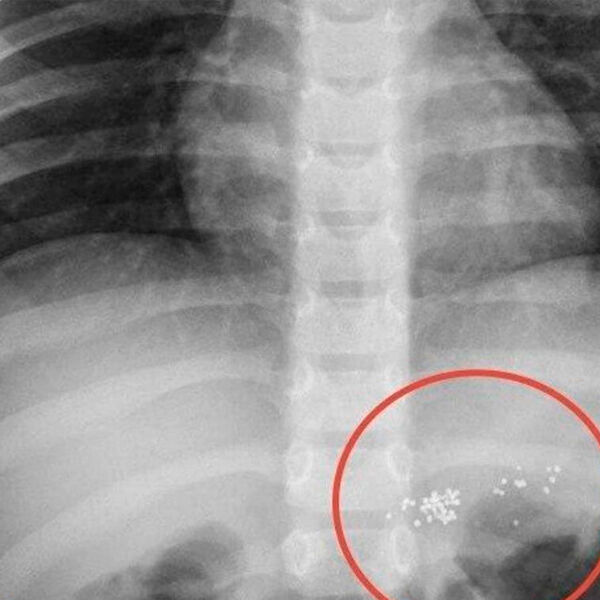

Врачи Новоуренгойской центральной городской больницы осмотрели маленького мальчика, который во время игры раскусил ртутный градусник и проглотил его содержимое. Об этом сообщили в пресс-службе медицинского учреждения.

«Проглоченная ртуть не опасна, токсичны только ее пары. Поэтому ребенка обследовали и оставили на несколько дней под амбулаторным наблюдением», — пояснили в пресс-службе больницы.

Врачи отметили, что ртуть, попавшая в желудок, пройдет по пищеварительному тракту и выйдет с калом. Медики некоторое время наблюдали за пациентом, убедившись, что все хорошо, ребенка отпустили.